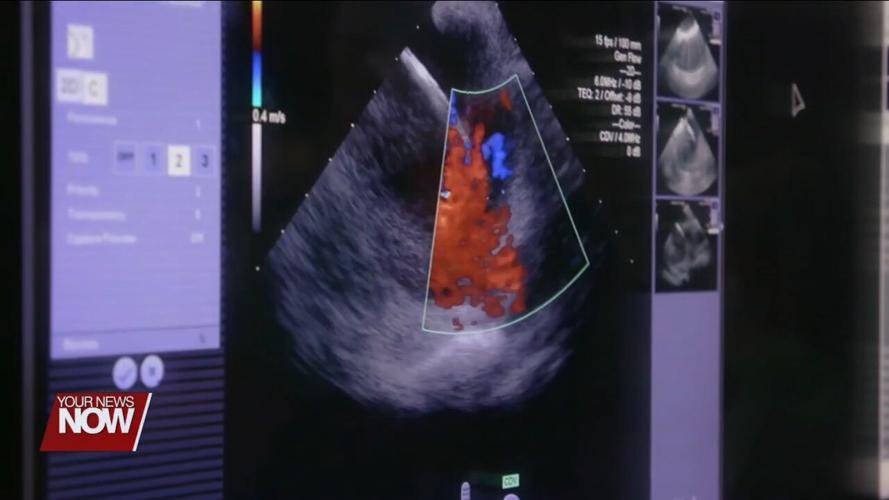

When medication failed to correct Amanda's AFib, her best option became a heart ablation, a surgical procedure that uses high energy to create a lesion in the precise location that is throwing off the heart's rhythm. While it's an effective treatment, it can also cause damage to the esophagus, which lies just five millimeters away.

"That thermal effect can result in an injury to both organs, where you get this communication, which becomes a very serious life-threatening problem," explained Emile, Daoud, MD at the Ohio State Wexner Medical Center.